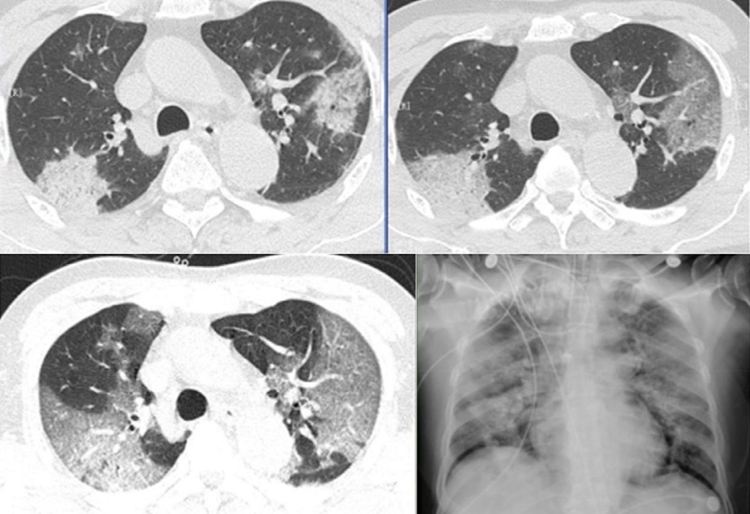

COVID-19 атакува белите дробове на заразения, нещо което много добре се вижда в снимката от компютърната томография. Ако това изображение се качи в Huawei Cloud, изкуственият интелект го анализира и прави диагностика. Нещо повече, изкуственият интелект определя стадия и тежестта на инфекцията. Новия ИИ е обучен и продължава да се обучава чрез непрекъснато нарастваща база данни от примери на заразени с COVID-19 пациенти.

Резултатът става готов след две минути, а нивото на ефективност е 98%. Това не е окончателна диагноза и е желателно тя да бъде потвърдена от лекар. Но полученият резултат е много добра алтернатива на традиционните анализи, които се изготвят за около три дни. Освен това, процесът изисква минимални усилия от страна на медицинския персонал.